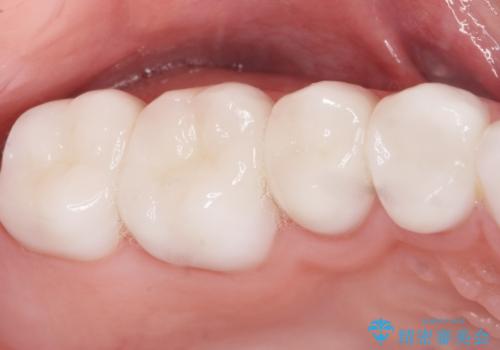

綺麗な仕上がりにご満足下さいました。

奥歯の咬み合わせも良くなったと喜んで頂けました。

患者様の理想とする韓流アイドルの写真を技工士さんに送り、最終的なクラウンの形や色をできるだけ理想に近づけられるよう努めました。

クラウンの種類:オールセラミッククラウン スタンダード